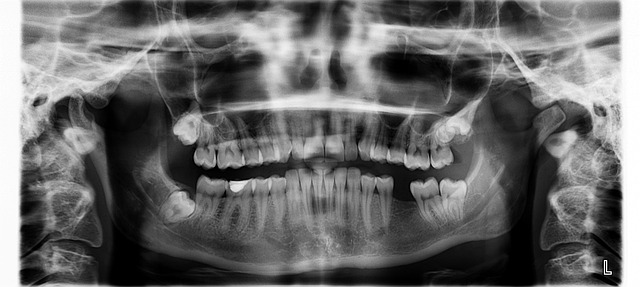

- 1. 초기 상담·정밀 진단 — 파노라마·3D CT로 뼈 조건과 신경 위치를 확인하고 맞춤 임플란트 시술과정을 설계

전신 병력과 구강 상태를 평가한 후 X-ray·3D CT로 뼈 높이·폭·밀도, 신경·상악동 위치를 분석합니다. 이 데이터가 곧 임플란트 시술과정의 설계도이며, 필요한 시술(뼈 이식·상악동 거상 등), 예상 내원 횟수, 잠정 기간을 결정합니다. 정밀 진단의 정확도가 전체 과정의 예측 가능성을 좌우합니다.